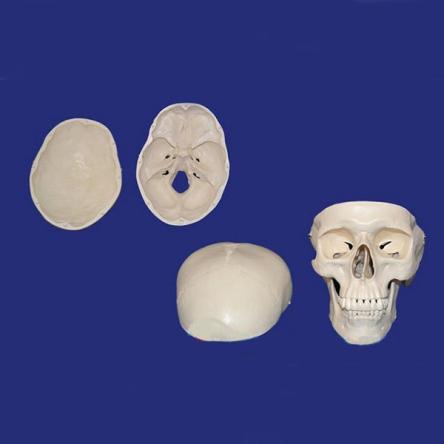

Детальная модель черепа человека A014 в натуральную величину с изображением всех детальных структур. Съемный свод черепа позволяет изучить внутреннее строение. Модель подходит для изучения в медицинских учебных учреждениях.

Модель разборная, из 3-ти частей.

Наша модель не просто состоит из 3-х частей (основной части, крыши и нижней челюсти), но и отличается тем, что имеет съёмные зубы. Нижняя челюсть подвижно соединена с основанием, крыша фиксируется на основании с помощью крючков.

При необходимости, крышу можно снять для изучения внутренней поверхности. черепа. Всё это делает данный муляж лучшим выбором для студентов-медиков, для школ и самообразования, к тому же являясь оригинальным медицинским подарком.